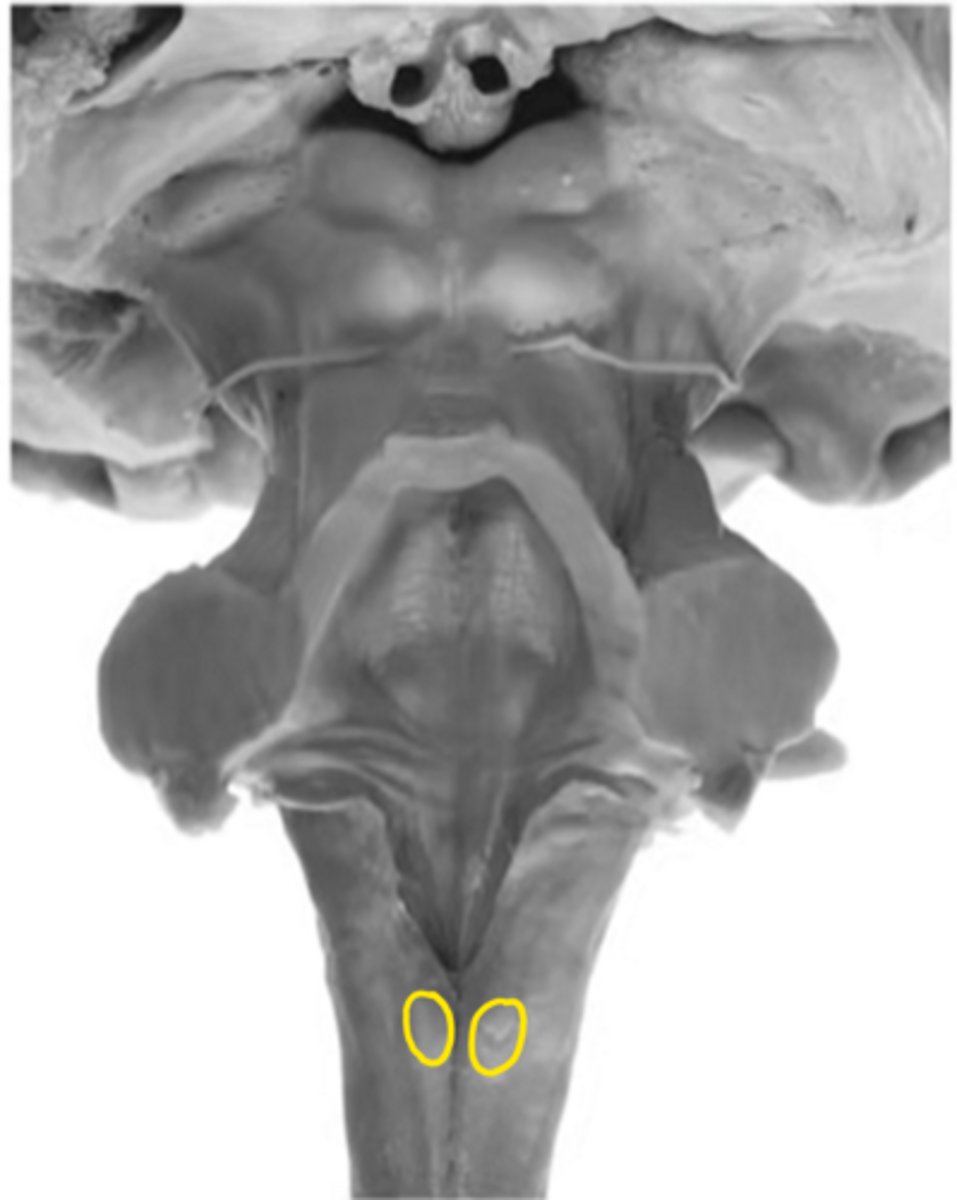

closed medulla

ID the brainstem level